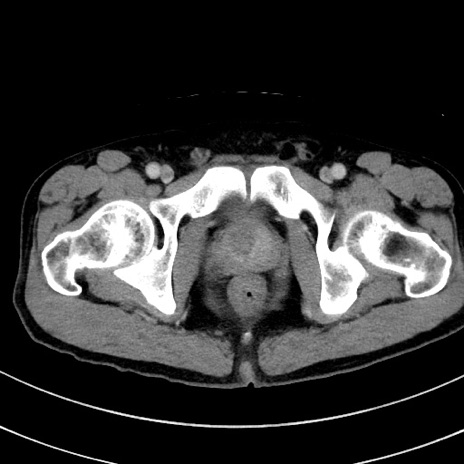

冠状断像

【症例】 60歳代男性

【主訴】 黒色吐物

【現病歴】 4日前から嘔気自覚、2日前の朝食後にも嘔気あり、自分で手で嘔吐反射起こし嘔吐したところ血が混ざっていたため受診。

【既往歴】 5年前汎発性腹膜炎を伴う急性虫垂炎で手術、高血圧、前立腺肥大症、高脂血症

【身体所見】 腹部正中に手術癩痕あり 腹部平坦・軟圧痛なし膨満感あり

【データ】WBC 8400、CRP 4.54